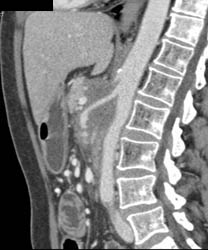

Chronic Pancreatitis